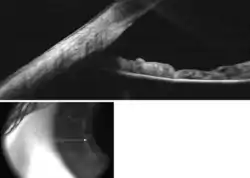

The EZ ratio method is one way to calculate the estimated anterior chamber depth.[2] To start, the patient looks at a target in the distance with one eye covered. The examiner takes a digital photograph of the open, examined eye, from the side, perpendicular to the visual axis (a profile photograph).

The following parameters then need to be measured in the photograph, using a personal computer or a smartphone (figures 1,2):

1. The pixel distance between the limbus (the junction between clear cornea and white sclera) and the front of the cornea. This distance is referred to as Z.

2. The pixel distance between the limbus and the centre of the pupil. This distance is referred to as E.

E:Z ratio is the arithmetic ratio between E and Z.

This ratio is linearly correlated with the depth of the anterior chamber with the following equation:

Anterior chamber depth (expressed in millimetres) = -3.3 x EZ ratio + 4.2

This estimate has been shown to be accurate with a 95% confidence interval of +/– 0.33 mm error, when compared to measurements of the anterior chamber depth by Scheimpflug photography.[2]